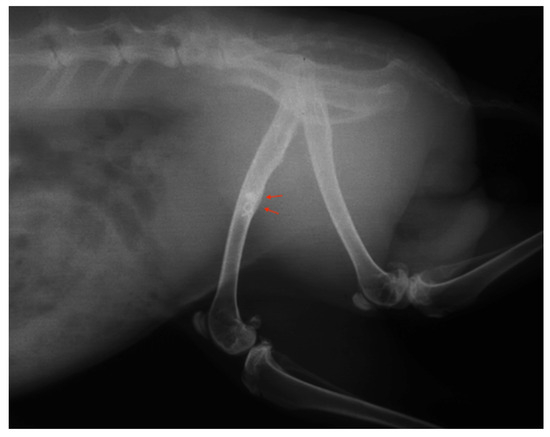

3.4. Radiographic Assessment